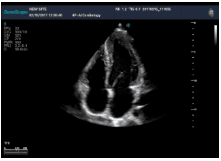

不同的探頭對應(yīng)于不同的臨床領(lǐng)域,不同的探頭頻率也應(yīng)用于不同的人體組織。超聲波在人體中的衰減與探頭頻率有關(guān),探頭頻率越高,穿透力越弱,分辨率越高,而探頭頻率越低,穿透力越強(qiáng),分辨率越低。因此在檢查淺表器官時應(yīng)選用高頻探頭,而檢查深部臟器時則選用穿透性強(qiáng)的低頻探頭。

Mark點:每一把探頭都有一個mark點,是用于定位方向, mark點一側(cè)始終對應(yīng)著圖像S點(圖像箭頭標(biāo)識)一側(cè)。